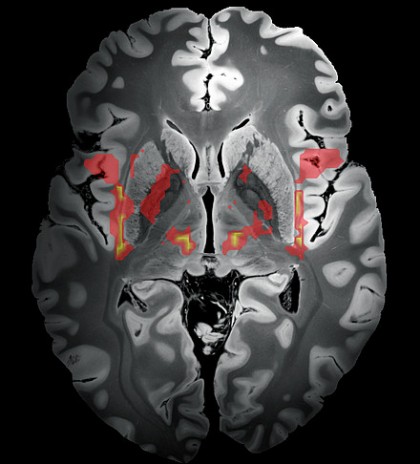

Cercetătorii au reușit să demonstreze faptul că aproape toate leziunile cerebrale ale pacienților, indiferent de locația lor exactă în creier, au făcut parte dintr-o rețea neuronală comună care cuprinde o gamă largă de zone, inclusiv cortexul insular, circumvoluția cingulată, talamusul sau cerebelul. Unul dintre primii autori ai studiului, Bassam Al-Fatly, explică: „Aceste structuri sunt distribuite aproape în întregul creier și au o gamă largă de funcții, de la controlul motor până la procesarea emoțiilor. Acum știm că aceste regiuni ale creierului formează o rețea și că, de fapt, ele ar putea provoca tulburări de tic”.

foto: Zonele colorate denotă părți ale rețelei neuronale care este capabilă să genereze ticuri. © Charité | Bassam Al-Fatly